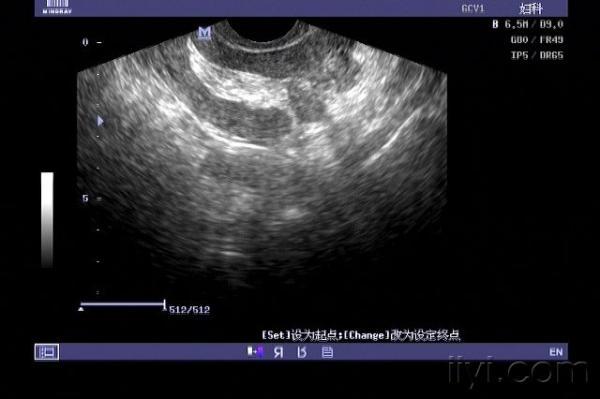

子宫穿孔的超声诊断

超声典型病例子宫穿孔

正常子宫彩超图

子宫穿孔彩超下表现

子宫穿孔超声表现图